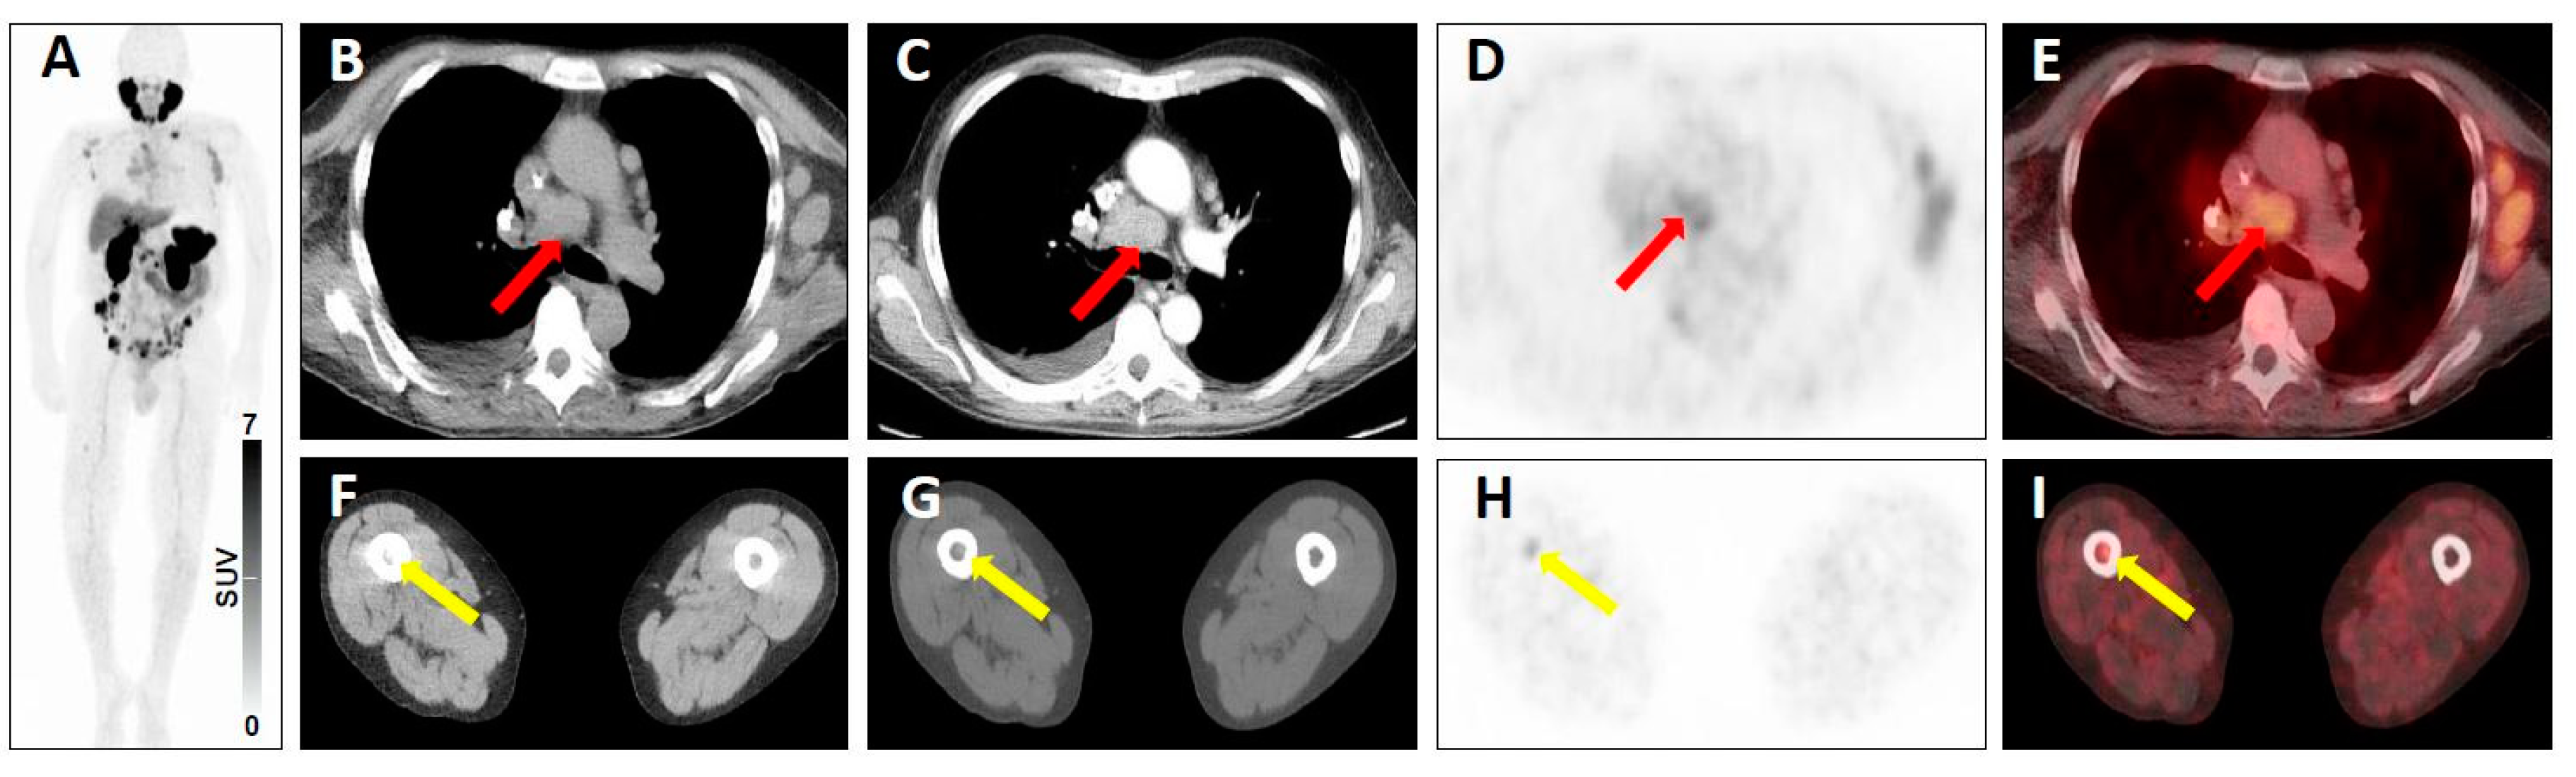

| 3C | - Intense breast uptake on SSTR-PET [20,21] - Intense uptake in the Musculus vastus lateralis [18] | - High level of radiotracer uptake in a lung nodule in a patient with low level of serum prostate-specific antigen [19] - Substernal thyroid nodule with radiotracer uptake (and without further work-up) [21,72] | |

| 3D | - Single liver lesion without SSTR expression but finding on conventional imaging [20] - Modest/No radiotracer uptake in the primary of the lung, with intense radiotracer uptake on 2-deoxy-2-18F-fluoro-d-glucose PET two weeks later [18] | - Prostate cancer (PC) of neuroendocrine origin [19] - Non-radiotracer-avid lung nodule in a patient with biochemically recurrent PC [19] | |